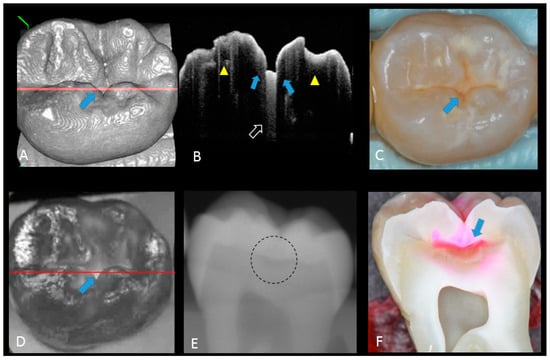

2. Materials and Methods

2.1. Specimen Preparation

2.2. Photography and X-ray Imaging

2.3. Optical Coherence Tomography

2.5. Validation of the Actual Scores